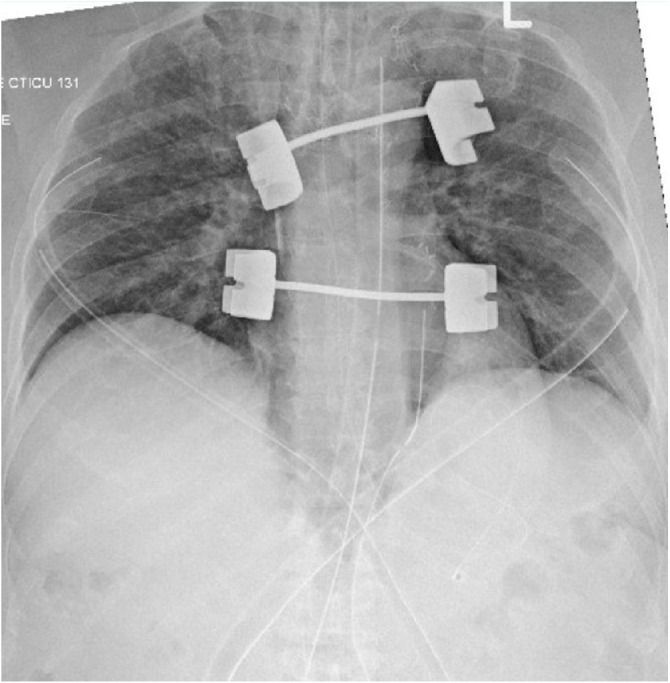

Case presentation: We present a case of REPE in a 64-year-old male undergoing elective coronary artery bypass grafting. Despite an uneventful surgery and standard perioperative management, the patient developed REPE, manifested with increased airway pressures, blood-tinged secretions, and compromised oxygenation post-CPB. Immediate intervention comprising mechanical ventilation adjustments, diuretics, and vasopressor support was initiated to facilitate recovery. The pulmonary edema resolved within 24 hours after the surgery, and the patient was transferred to the surgical high-dependency unit (HDU) on the third postoperative day.